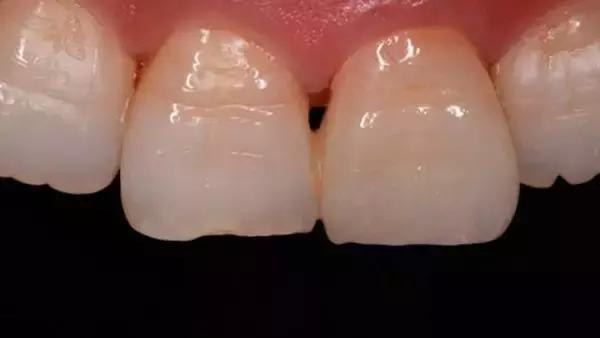

所谓的黑三角,是指牙龈不能完全覆盖两个牙齿的牙颈部与接触点之间的间隙时,那个呈三角形的空洞区域。其实,黑三角最让人恐惧的并非是它不好看甚至“说话漏风”,而在于黑三角无法自我修复,甚至可能越来越严重。由于有了这个额外的空洞,很容易造成食物嵌塞,更是给细菌营造了一个良好的储存环境,对口腔健康大大不利。